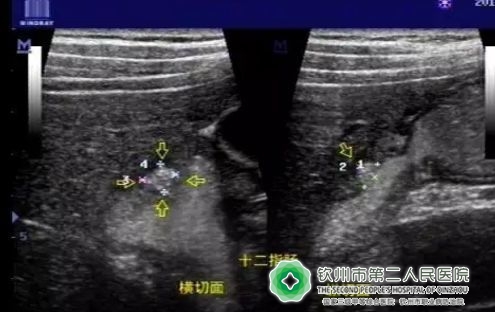

(十二指肠球溃疡)